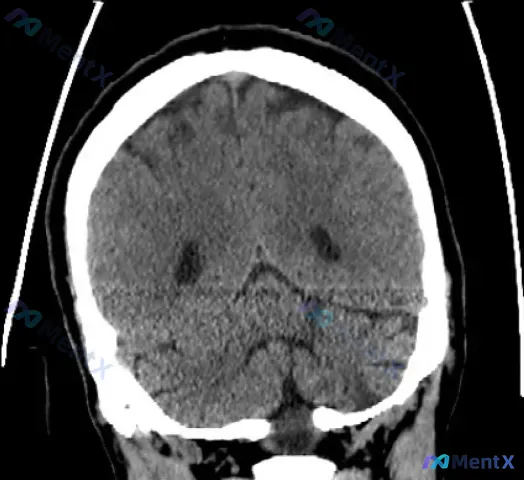

临床定位指向左侧小脑+脑桥梗死,但CT平扫未见异常,下一步该怎么处理?

- 临床定位指向左侧小脑+脑桥受累(有相应的神经功能缺损描述)

- 但头部CT平扫(非增强)报告写的是:未见明显低密度灶,排除大面积脑梗死,中线结构正常,无出血

这份资料里其实有一个经典的神经科陷阱,尤其是对后颅窝的判断。